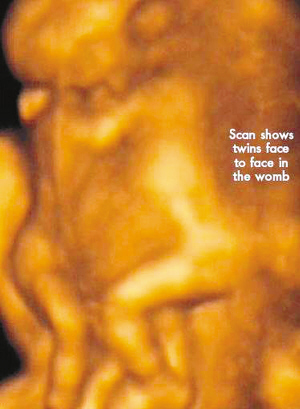

今年初,怀孕7周多的丽莎检查发现,怀上的竟是一对腹部紧紧相连的连体男婴。这对连体婴共享一只肝脏,虽然他们拥有各自的心脏,但两颗心脏却粘连在了一起。医生建议丽莎立即接受流产手术,他认为丽莎腹中的连体婴甚至无法活到她怀孕10周的时候。

丽莎每周都要到医院接受医学扫描,而她腹中的连体婴也让医生感到惊讶不已,因为他们已经打破了医生的死亡预言,一直在母亲子宫中坚强活到了现在。丽莎将于两周内接受剖腹产手术。